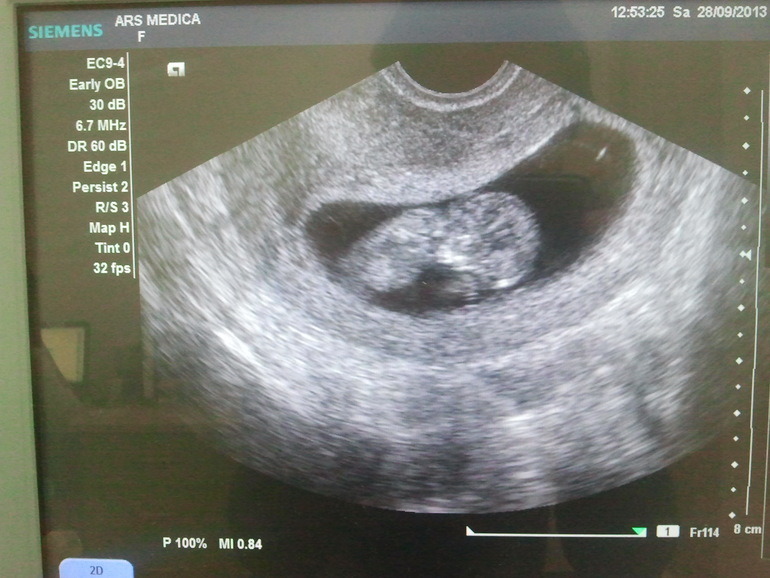

Ровно 11 неделек. УЗИ (дополнительно перед скринингом)

какой миленький малышок (тттт)!! а пол не сказали?

Нет не сказали, всё спрятал(а). Может на скрининге что–нибудь скажут, если вообще что–то скажут

Здорово ! Пусть и дальше все хорошо будет)он так интересно расположен) у меня лежит как будто на диване, горизонтально ровно...

Спасибо! Еще столько раз успеет поменять свое расположение... думаю еще и не такие причуды можно увидеть